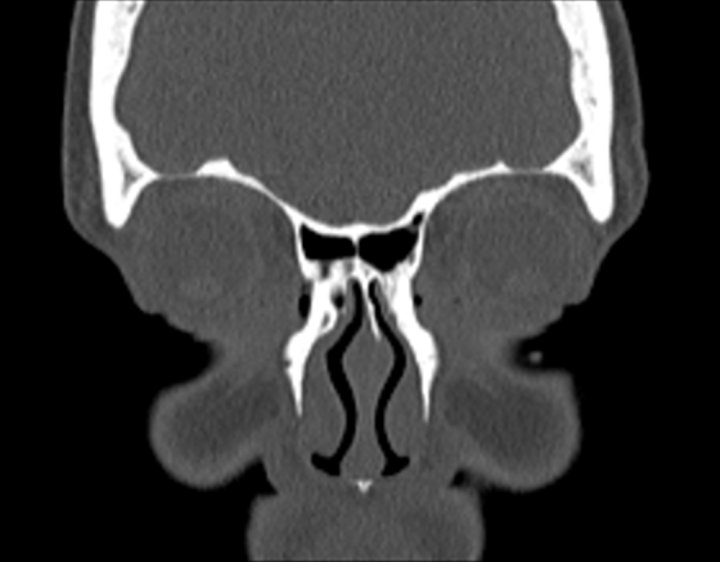

Click any image for labels.